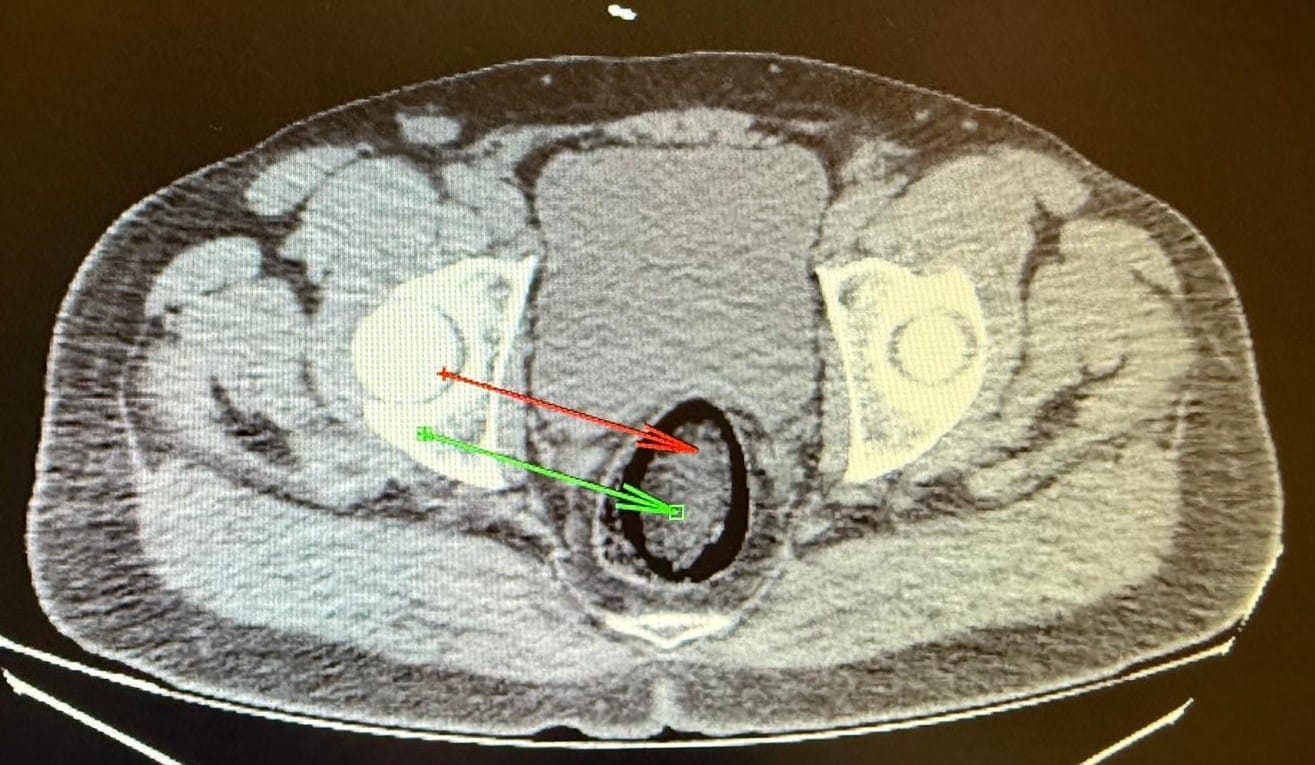

Kars Harakani Devlet Hastanesi'ne götürülen F.H.'nin çekilen röntgeninde, makatında uyuşturucu tespit edildi. İranlı yolcunun makatına zulaladığı 105,98 gram metamfetamin, cerrahi operasyonla çıkarıldı.